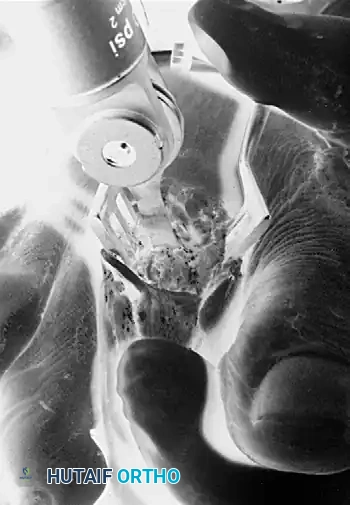

Retrograde Pinning:

Reverse the drill and drive the pin retrograde through the remaining portion of the proximal phalanx shaft.

Diagrammatic representation: Pin reversed and driven retrograde through the remaining portion of the shaft of the phalanx and across the MTP joint.

Exit the articular surface of the proximal phalanx near its center. Stand at the head of the table, holding the toe concentrically reduced at the MTP joint (viewing the toe as the patient would see it). Have an assistant drill the pin into the metatarsal shaft.

Intraoperative view of retrograde pinning through the proximal phalanx across the metatarsophalangeal joint.